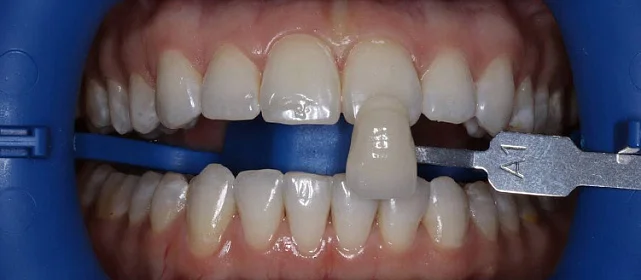

Диагностика

КЛКТ, интраоральное сканирование, пародонтологическое обследование. Подвижности зубов нет, глубина зондирования — в пределах нормы.

Результат

полное выравнивание зубных рядов без удаления зубов. Рецессия десны не прогрессировала (контроль по КТ через 12 месяцев). Пациентка носит несъёмные ретейнеры

и ночные капы.